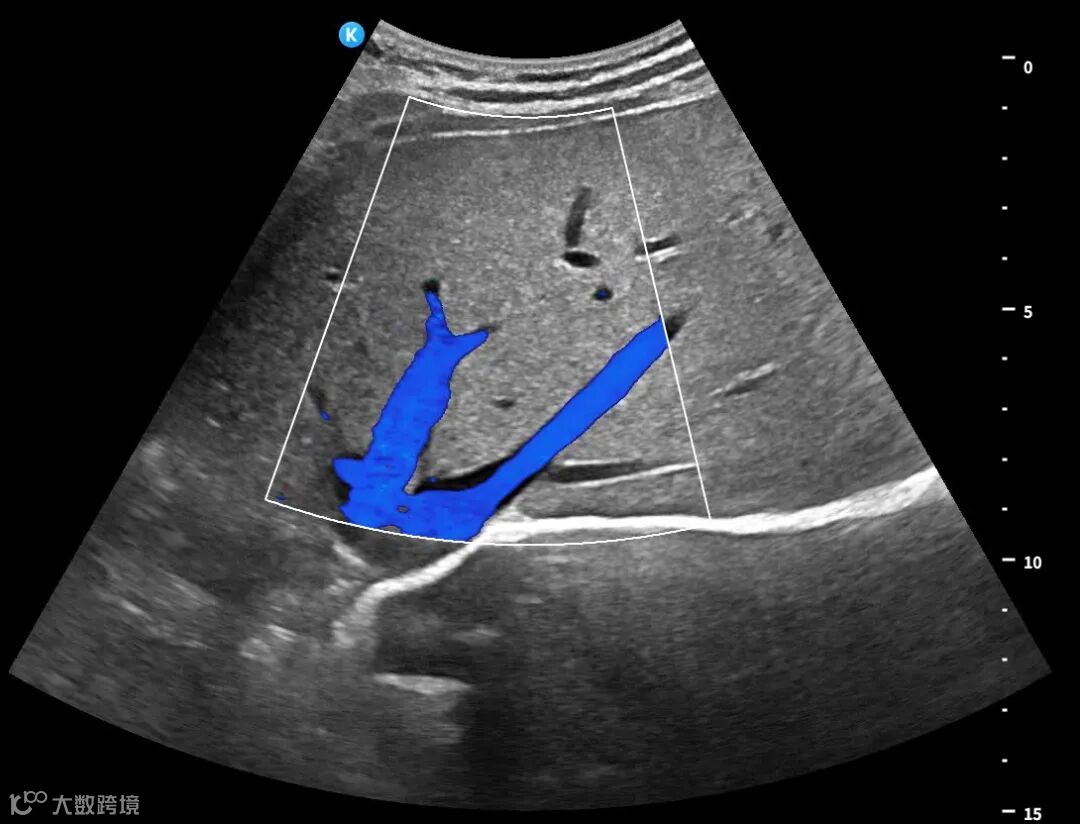

深圳鲲为科技有限公司是以突破性原创技术引领,并致力于下一代超分辨超声开发的专业影像设备公司。